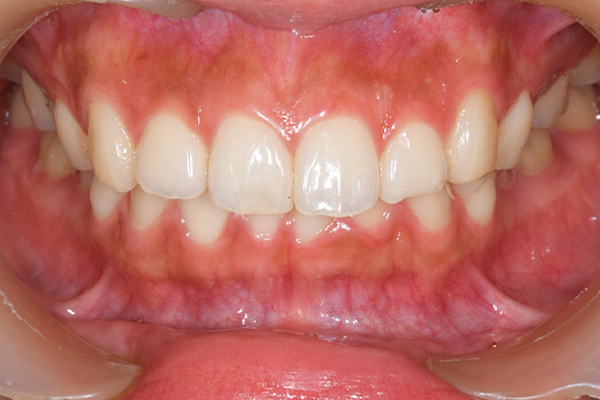

症例写真(治療後)

担当医師所見

矯正装置をつけています。だんだん八重歯が動いてきているのがわかります。今回のケースでは、抜歯を行わずに矯正ができました。

治療後:

矯正治療と虫歯の治療すべて終わったときの写真になります。見た目も最初の頃とは全く違いますし、お口の中もすごく綺麗です。